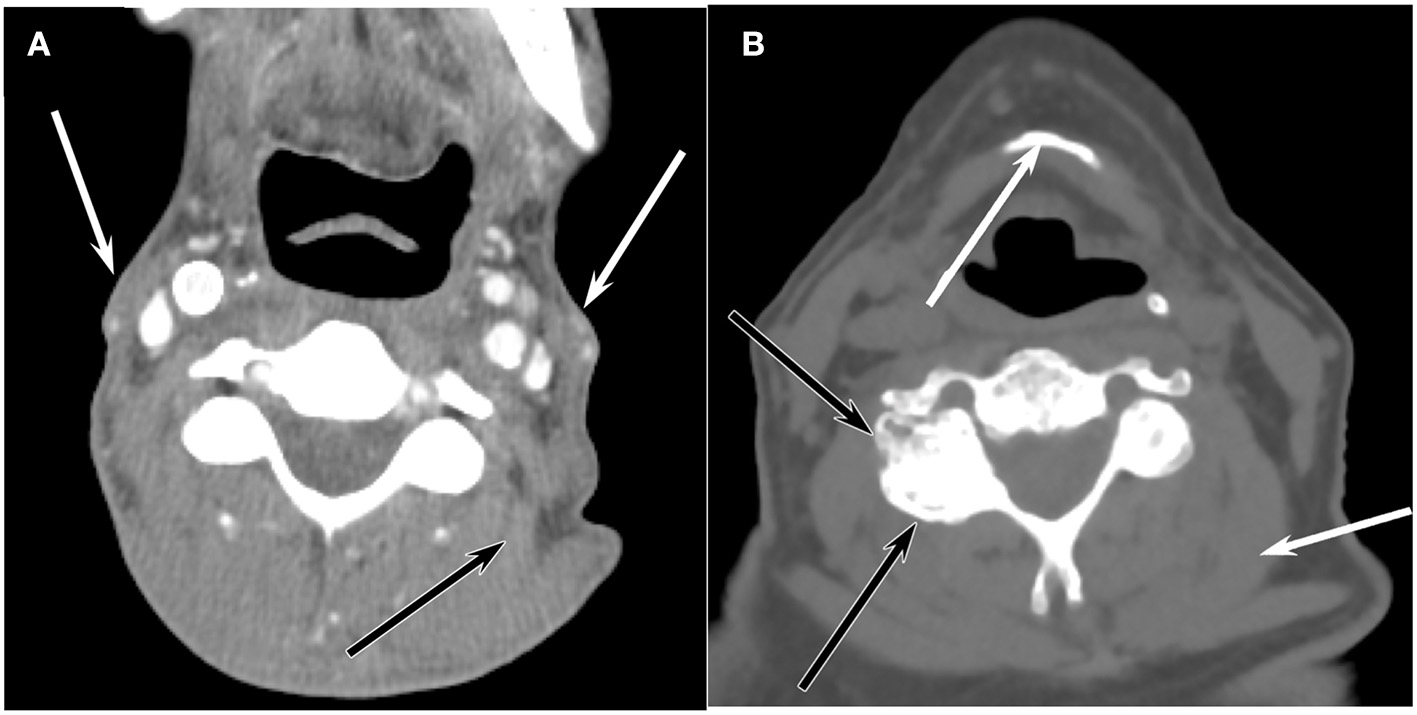

Neck CT imaging performed in routine cancer surveillance was identified for survivors. Scans within 6 months of a survivor NDI survey were used for the study. CT scans were performed on GE Lightspeed systems with 64 data channels. Acquisition parameters included: 100 kVp, automated mA (generally 100–200), FOV 18–25 cm, matrix 512 × 512, pitch 0.53. Axial 1.25 mm-thick reconstructions were created with bone and soft tissue kernels, which were then reformatted into sagittal and coronal planes. Images were evaluated by a head and neck radiologist with 20 years of experience in practice blinded to neck disability scores and patient characteristics. The degree of degeneration was categorized based on subjective analysis of the entire neck rather than relying on a single cervical level since degenerative disease and muscle loss are often non-uniform through the cervical spine. Disc and facet degeneration were rated on a 5-point scale (1 = none, 2 = mild, 3 = moderate, 4 = severe, 5 = complete disease) with examples seen in Figure 1.

Figure 1. Axial CT representations of (A) Enhanced axial CT of a 56-year-old man at the level of C3 shows marked atrophy of the sternocleidomastoid muscles (white arrows) and paraspinal muscles such as the levator scapulae muscle (black arrow), but there is no appreciable degenerative disease in the facet joints or discs. (B) Unenhanced axial CT image at the level of C3 reveals extensive facet arthrophy (black arrows) and disc disease, but the muscle volume (white arrow) is normal for a 71-year-old man.